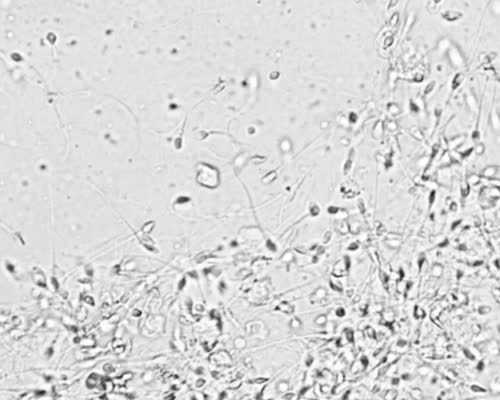

备孕多久算正常>精子、卵子都是很脆弱的,超过38度以上、甚至39度以上的高热对于他们都会有或多或少的影响,建议感冒时勤量体温,如果发现体温升高,应该及时给予降温治疗,比如物理降温或者应用临床常用的退烧药物包括阿司匹林,扑热息痛(或含扑热息痛的退烧药)等都可以在医生的指导下使用。有文献证实短期应用退烧药会减少出生缺陷的发生。